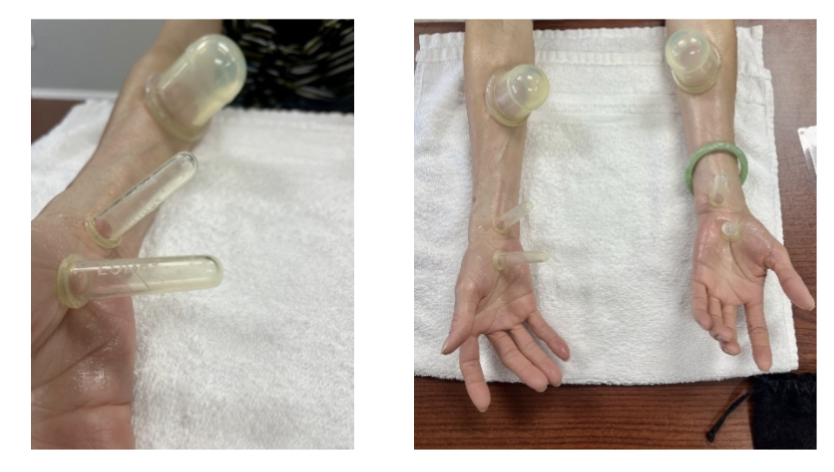

拔罐疗法作为腕管综合征理疗新方法的效果

文章审稿人:Rachel Reed Mohammadi, S.、Roostayi, MM、Naimi, SS 和 Baghban, AA (2019)。拔罐疗法的功效...